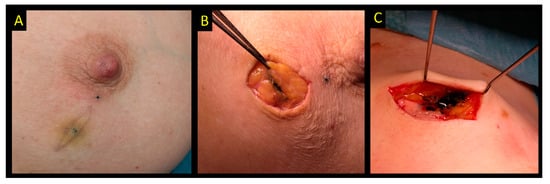

2.8. Carbon Suspension

| Carbon |

|